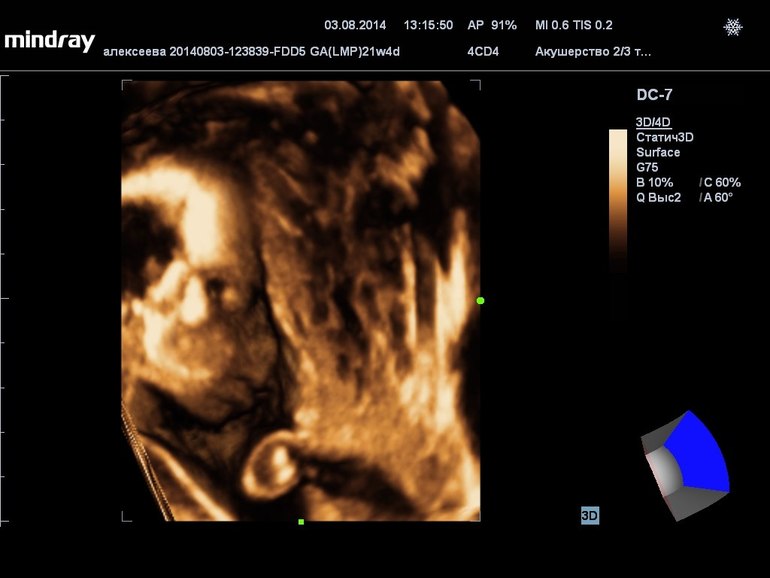

И фото узи на тех же неделях. Моя ежевичка сладкая

Она на этих 3д очень на мужа похожа! Но это нам повезло с аппаратом, качество хорошее, а на другом вообще ерунда была

Которое хорошее в ЦИРЕ у Справцевой, про нее тут много пишут. А фиговое у нас на районе